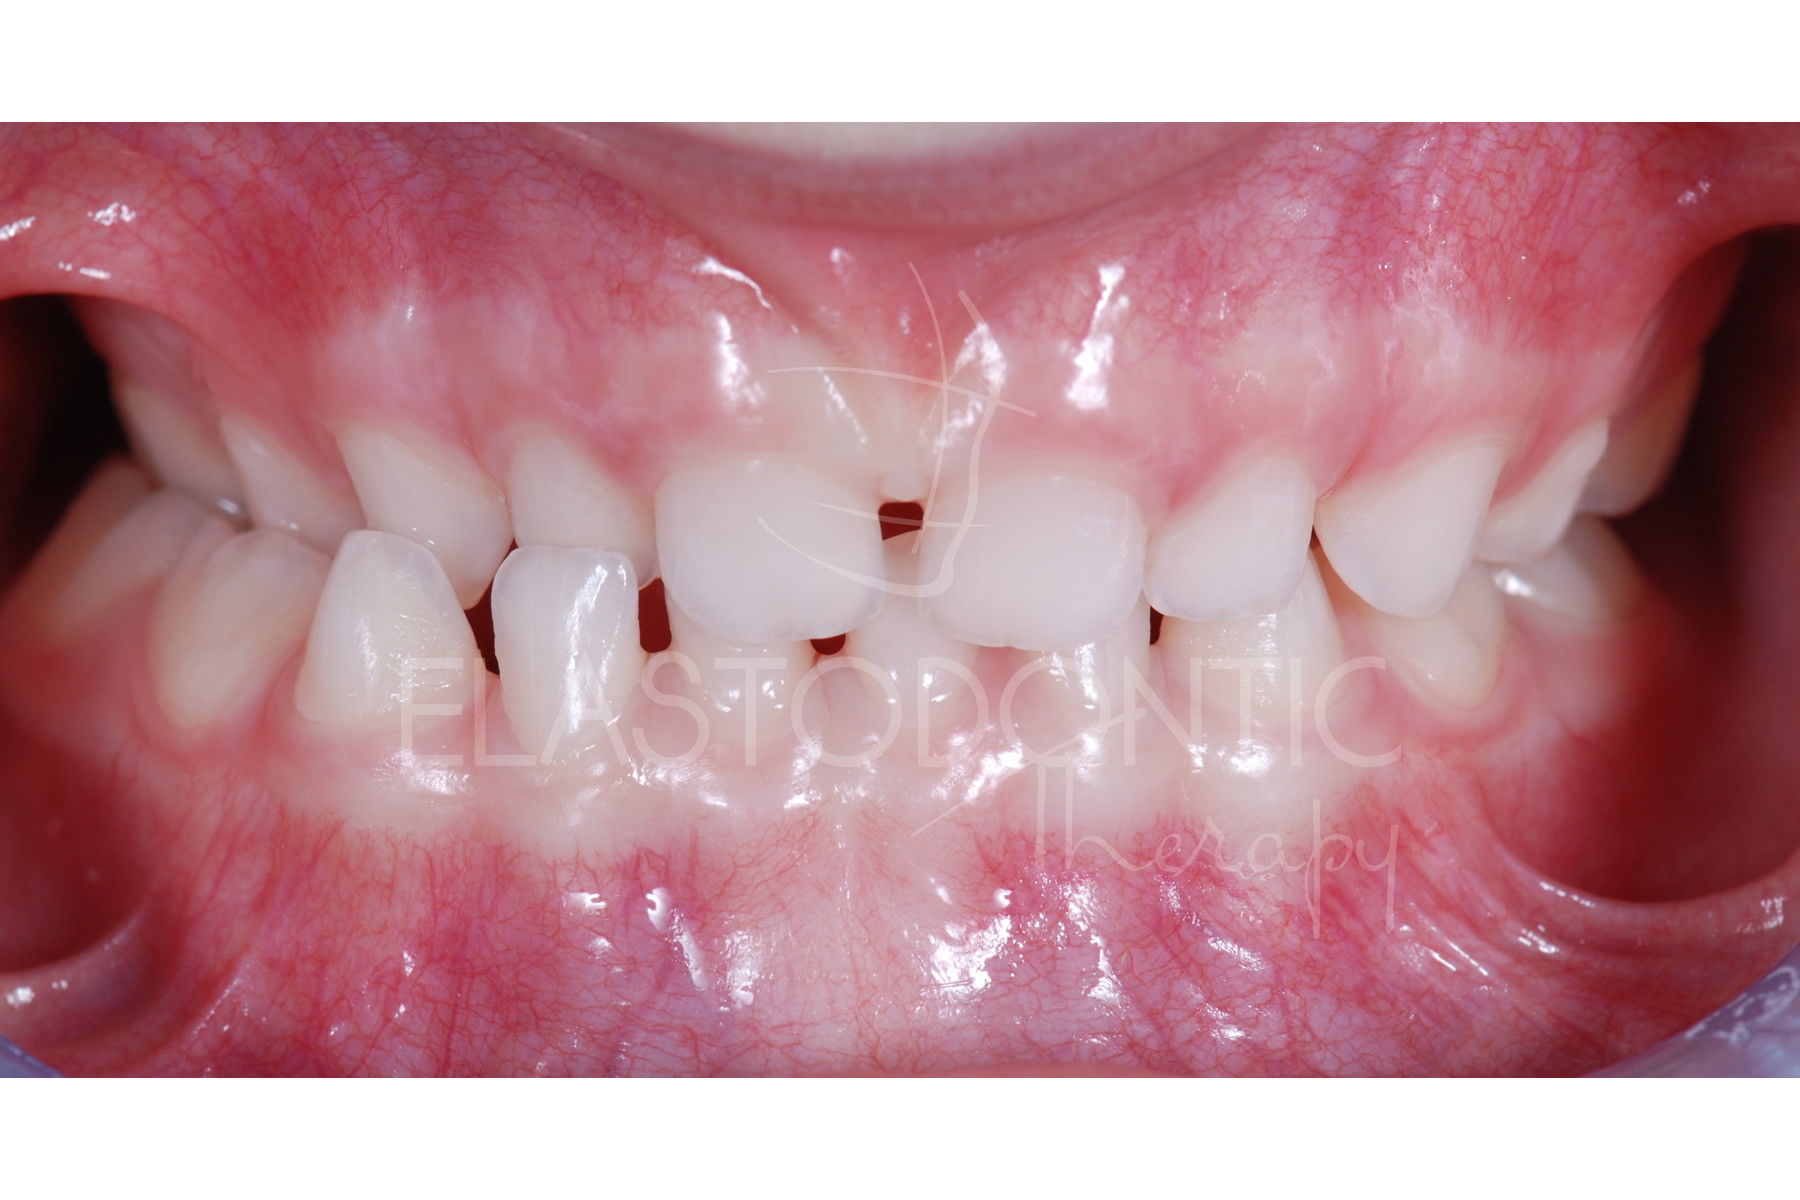

Morso Incrociato Monolaterale

Paziente di 3,5 anni

Gli elementi dentali superiori cadono all'interno degli inferiori sul lato Dx , morso incrociato monolaterale.

Palato stretto.

Respirazione orale.

L'ElastodonticTherapy® all'età di 3,5 anni è determinante per favorire una crescita armoniosa dellle strutture scheletriche e per favorire una regolare eruzione dei denti permanenti su basi ossee proporzionate.

Il brevissimo tempo di cura e la buona collaborazione del paziente rendono la terapia straordinariamente efficace e nello stesso tempo, poichè la situazione occlusale del paziente viene subito migliorata, la collaborazione dello stesso sarà sempre favorevole.